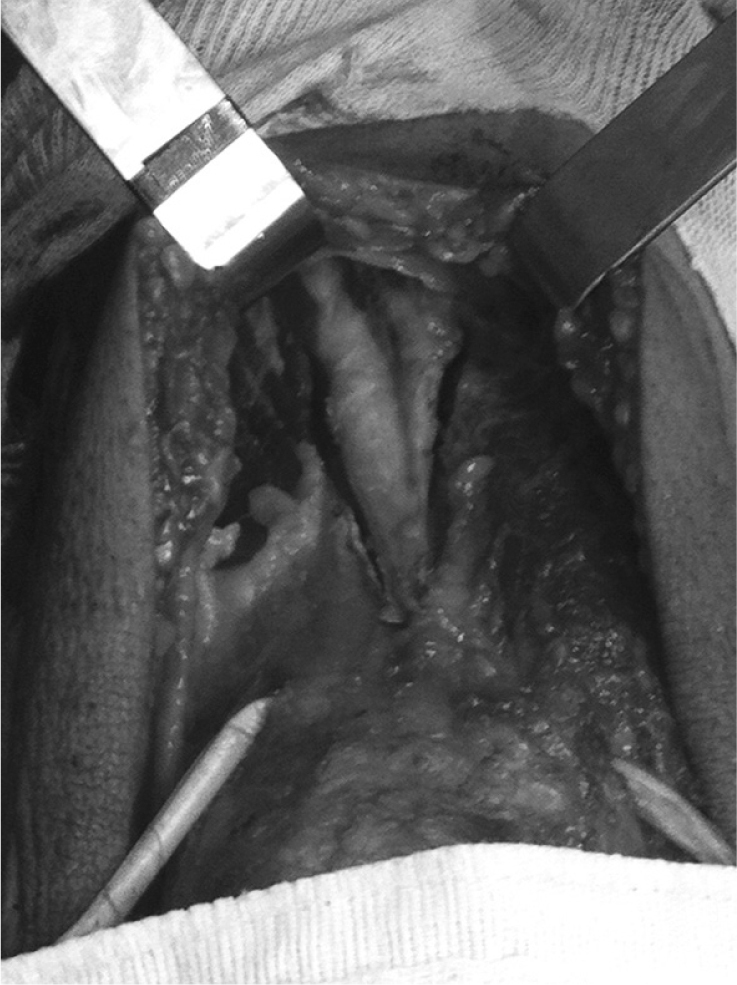

Fig. 1.

Ample anterior incision showing the semitendinosus and gracilis tendons repaired.